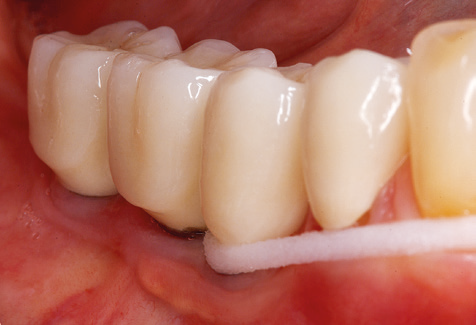

Of course, working tips for the cleaning of implant surfaces are also indispensable for SPT in patients fitted with implants. The implant cleaning attachment on the system used here is characterised by its tapered, hexagonal design. This design allows light, atraumatic penetration of the peri-implant pocket and displays a good cleaning performance (Fig. 7).

Following machine cleaning of the tooth and implant surfaces, the surfaces of the natural teeth are cleaned manually using standard hand instruments. When performing manual cleaning, particular attention must be given to maintaining the correct angle of application, appropriate sharpness, good support and working with the curette from apical to coronal. Either titanium or carbon curettes should be used for post-cleaning of the implant structures (Fig. 8). In addition to the use of ultrasonic devices, power jet devices can also be used in conservative dentistry. However, it must be taken into consideration that these procedures are not suitable for removing hard deposits and thus they cannot replace the use of hand instruments and ultrasonic instruments completely. In all cases, cleaning is followed by mechanical polishing of the accessible tooth and implant surfaces with polishing cups and polishing compounds (Fig. 9).